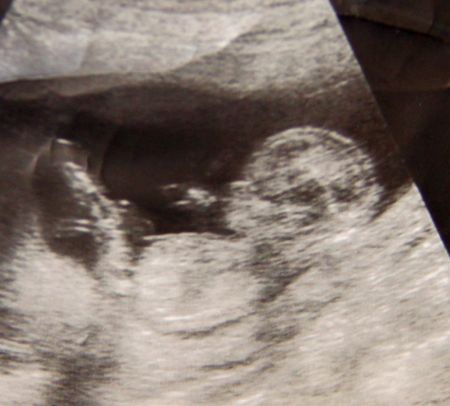

вот фото узи моей доченьки на 9,5 недель. Видно что с пальцем во рту))) Как можно такого готового человечка убить??

вы прикалываетесь! акушерских, от первого дня месячных. Ходила на первый скрининг, которрый на 10 недель назначают, но пришла чуть раньше, т.к. записалась так.